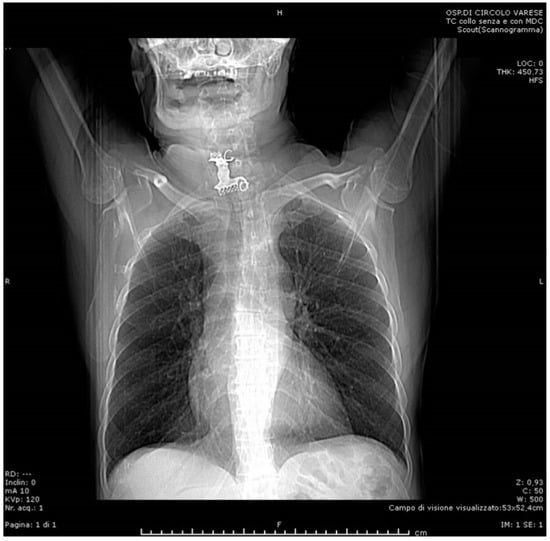

2. Case Presentation